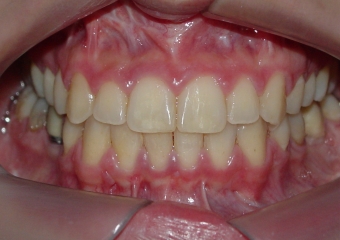

Mordida inicial

Mordida final